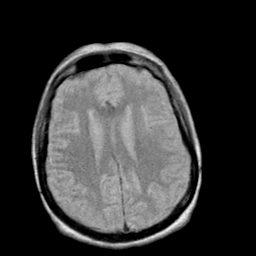

Creutzfeld-Jakob disease: proton density-weighted MR -- Slice #15

[Home][Help][Clinical] Slice 15